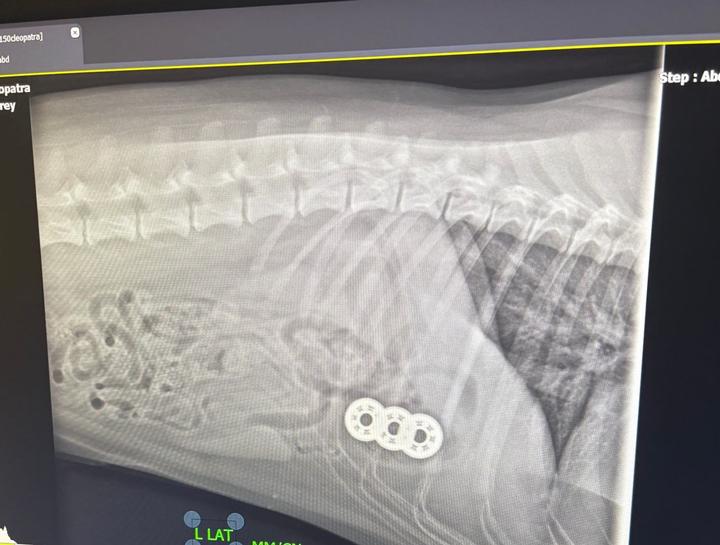

Pet Digital Radiology

Digital x-rays assist in diagnosing illness & injury.